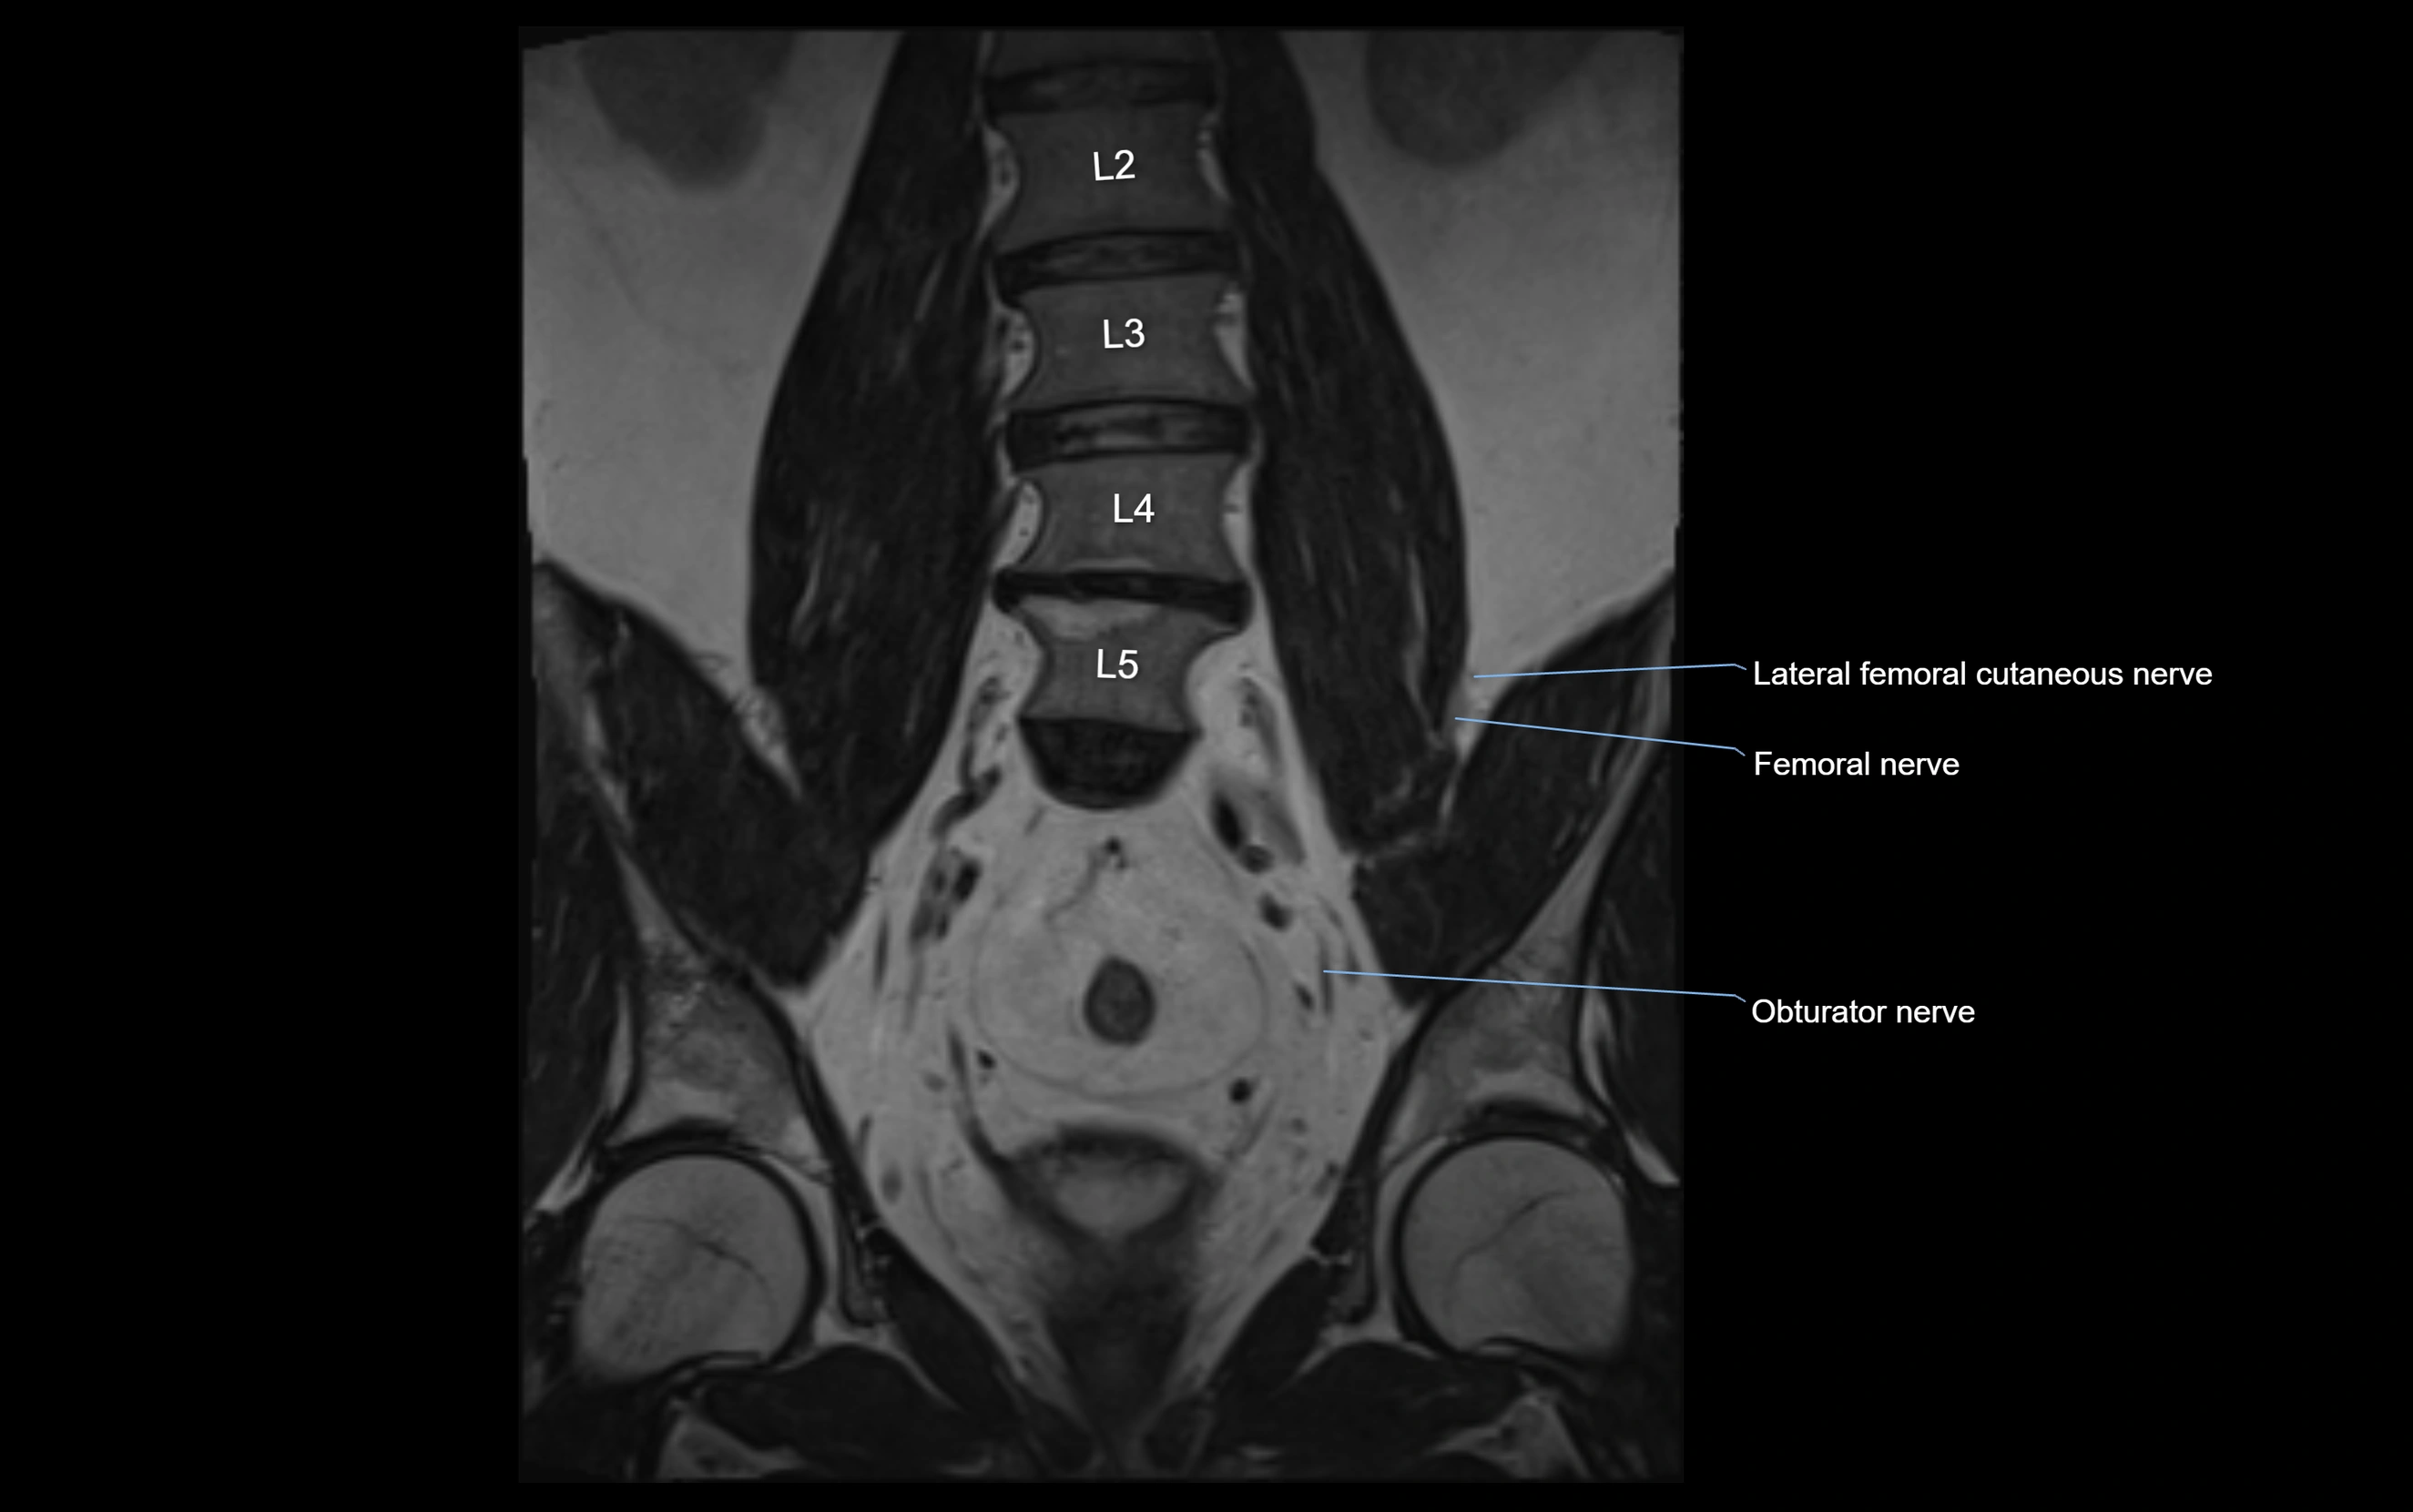

MRI Appearance

T1-weighted images:

• Nerve appears as a very thin low-to-intermediate signal intensity structure

• Surrounded by bright fat, aiding visualization

T2-weighted images:

• Nerve shows intermediate to mildly hyperintense signal compared to muscle

• Pathological involvement appears brighter

STIR (Short Tau Inversion Recovery):

• Normal nerve appears dark

• Inflamed or entrapped nerve appears bright hyperintense

3D T2 SPACE / CISS:

• Nerve appears intermediate to mildly hyperintense compared to muscle

• Surrounded by bright fat or CSF, improving visualization

• Best sequence for mapping small pelvic nerves such as the anococcygeal